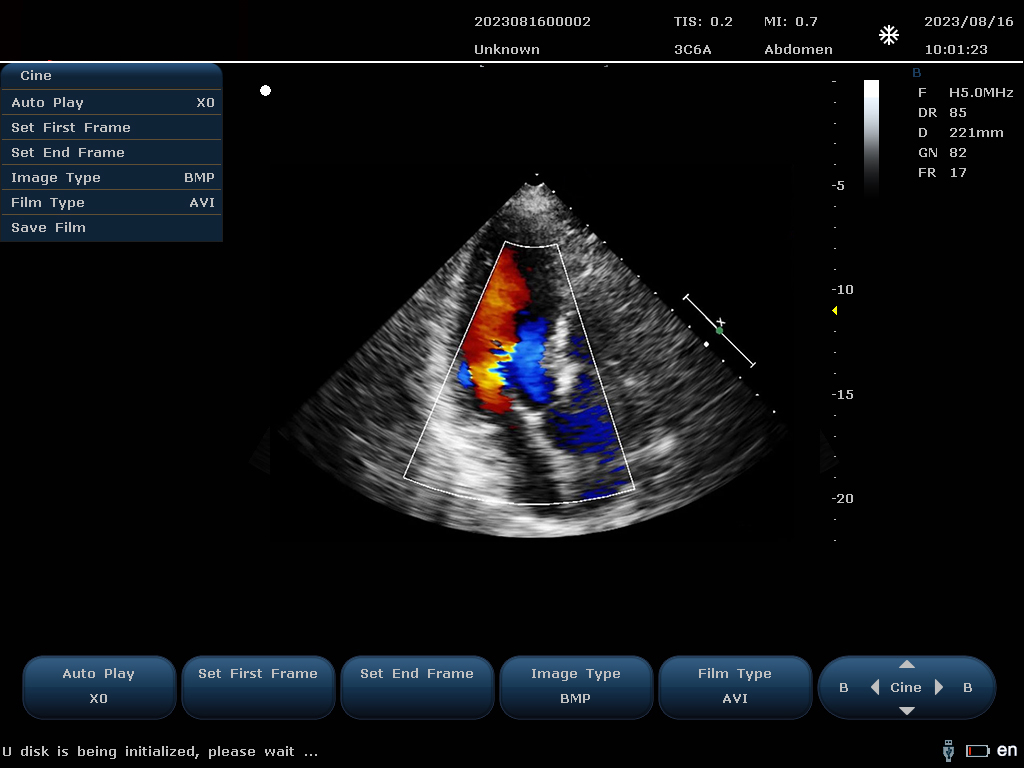

設(shè)備通過(guò)檢測(cè)這些頻移信號(hào),并利用復(fù)雜的信號(hào)處理技術(shù),包括傅立葉變換等,分析血流的方向、速度和分布。彩色編碼后,血流信息被疊加在傳統(tǒng)的黑白超聲二維圖像上,形成彩色多普勒?qǐng)D像,直觀顯示血流動(dòng)態(tài)。

最終,這些信息轉(zhuǎn)化為圖像顯示在屏幕上,醫(yī)生可以根據(jù)圖像中血流的顏色(通常紅色代表血流朝向探頭,藍(lán)色代表遠(yuǎn)離探頭)和亮度來(lái)判斷血流的性質(zhì)和異常情況,如血流速度增快可能指示狹窄,無(wú)血流區(qū)域可能意味著阻塞等。